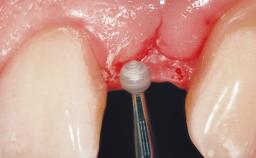

This 43-year-old male patient, a non-smoker, came to our practice because of a fracture of tooth 12 caused by a bicycle accident. Due to the combined para- and infrabony crown and root fracture, tooth extraction, and subsequent implant placement were suggested to the patient as the therapy of choice. The patient had high esthetic expectations with regard to the treatment outcome and asked for an immediate fixed provisional restoration. His individual esthetic risk profile summed up to a medium esthetic risk.

Placement Protocol Immediate implant placement

Socket Morphology Single-root socket